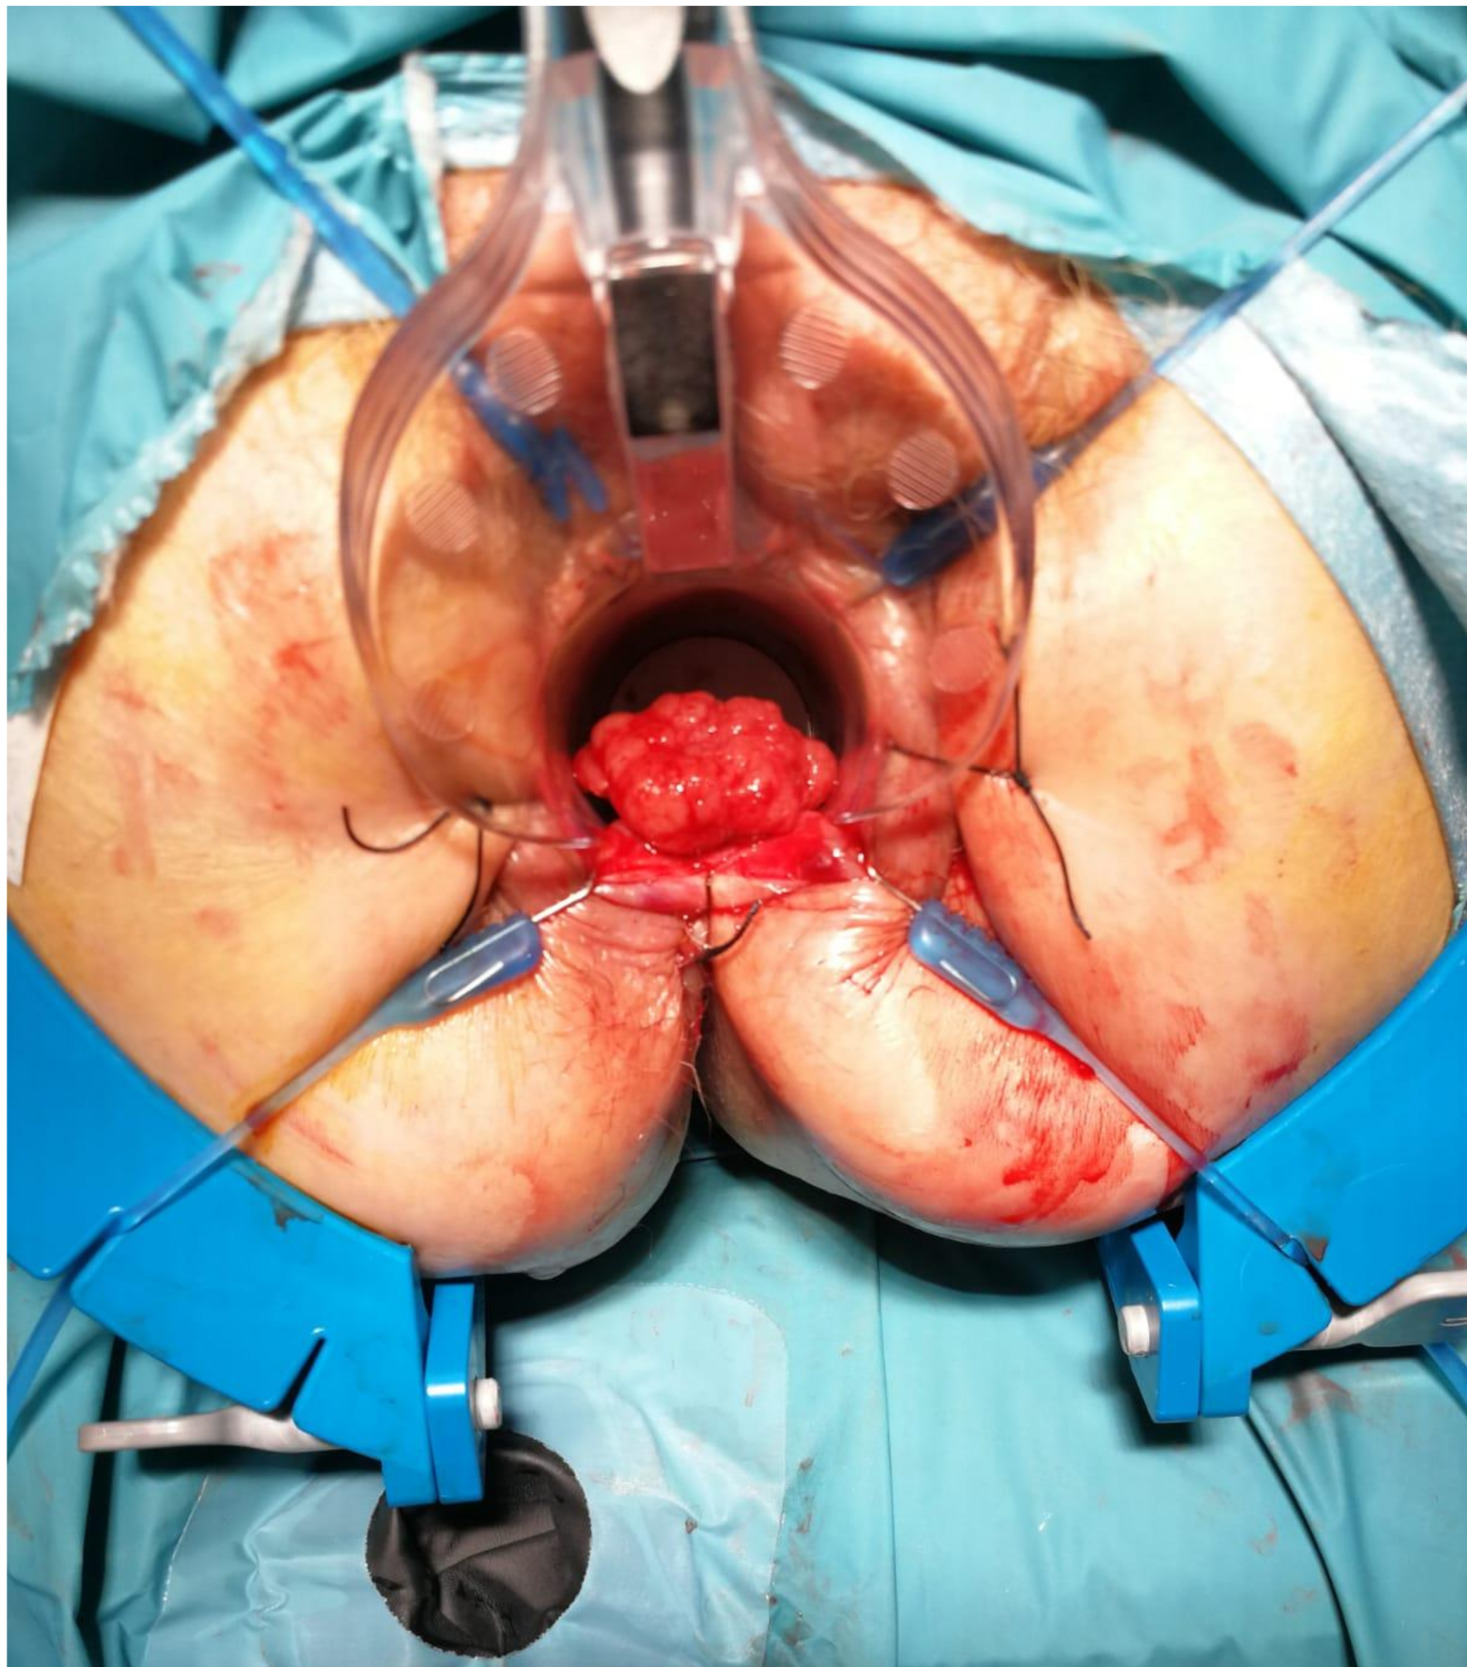

Inhomogeneous signal hyperintensity in T2-weighted sequences with a fluid/fluid level appearance, isointensity signal in T1-weighted sequences, no signal reduction in T1-weighted sequences in opposition of phase in agreement with the absence of a lipid component, no signs of signal restriction in diffusion (ADC 1.6), thin peripheral contrast enhancement, and thin septa in the structure were all features of the MRI. The lesion on the right posterolateral side appeared to affect the muscular coat, extending to the serosa raising suspicion for a teratomatous-type lesion. Following multidisciplinary consultation, surgical excision was planned. A transanal local excision was performed under general anesthesia (Figure 3). The patient’s postoperative course was uneventful, and he was discharged on the first postoperative day. Histopathological analysis revealed an edematous, ulcerated, and chronically inflamed segment of the large intestinal wall, containing lymphatic and intraparietal blood vessel ectasias consistent with hemolymphangioma. No postoperative complications were observed. The patient underwent regular follow-up evaluations, including proctological examinations, CT scans, and MRI studies (Figure 4) every six months for the initial two years, followed by annual assessments. At four years postoperatively, there is no evidence of disease recurrence.